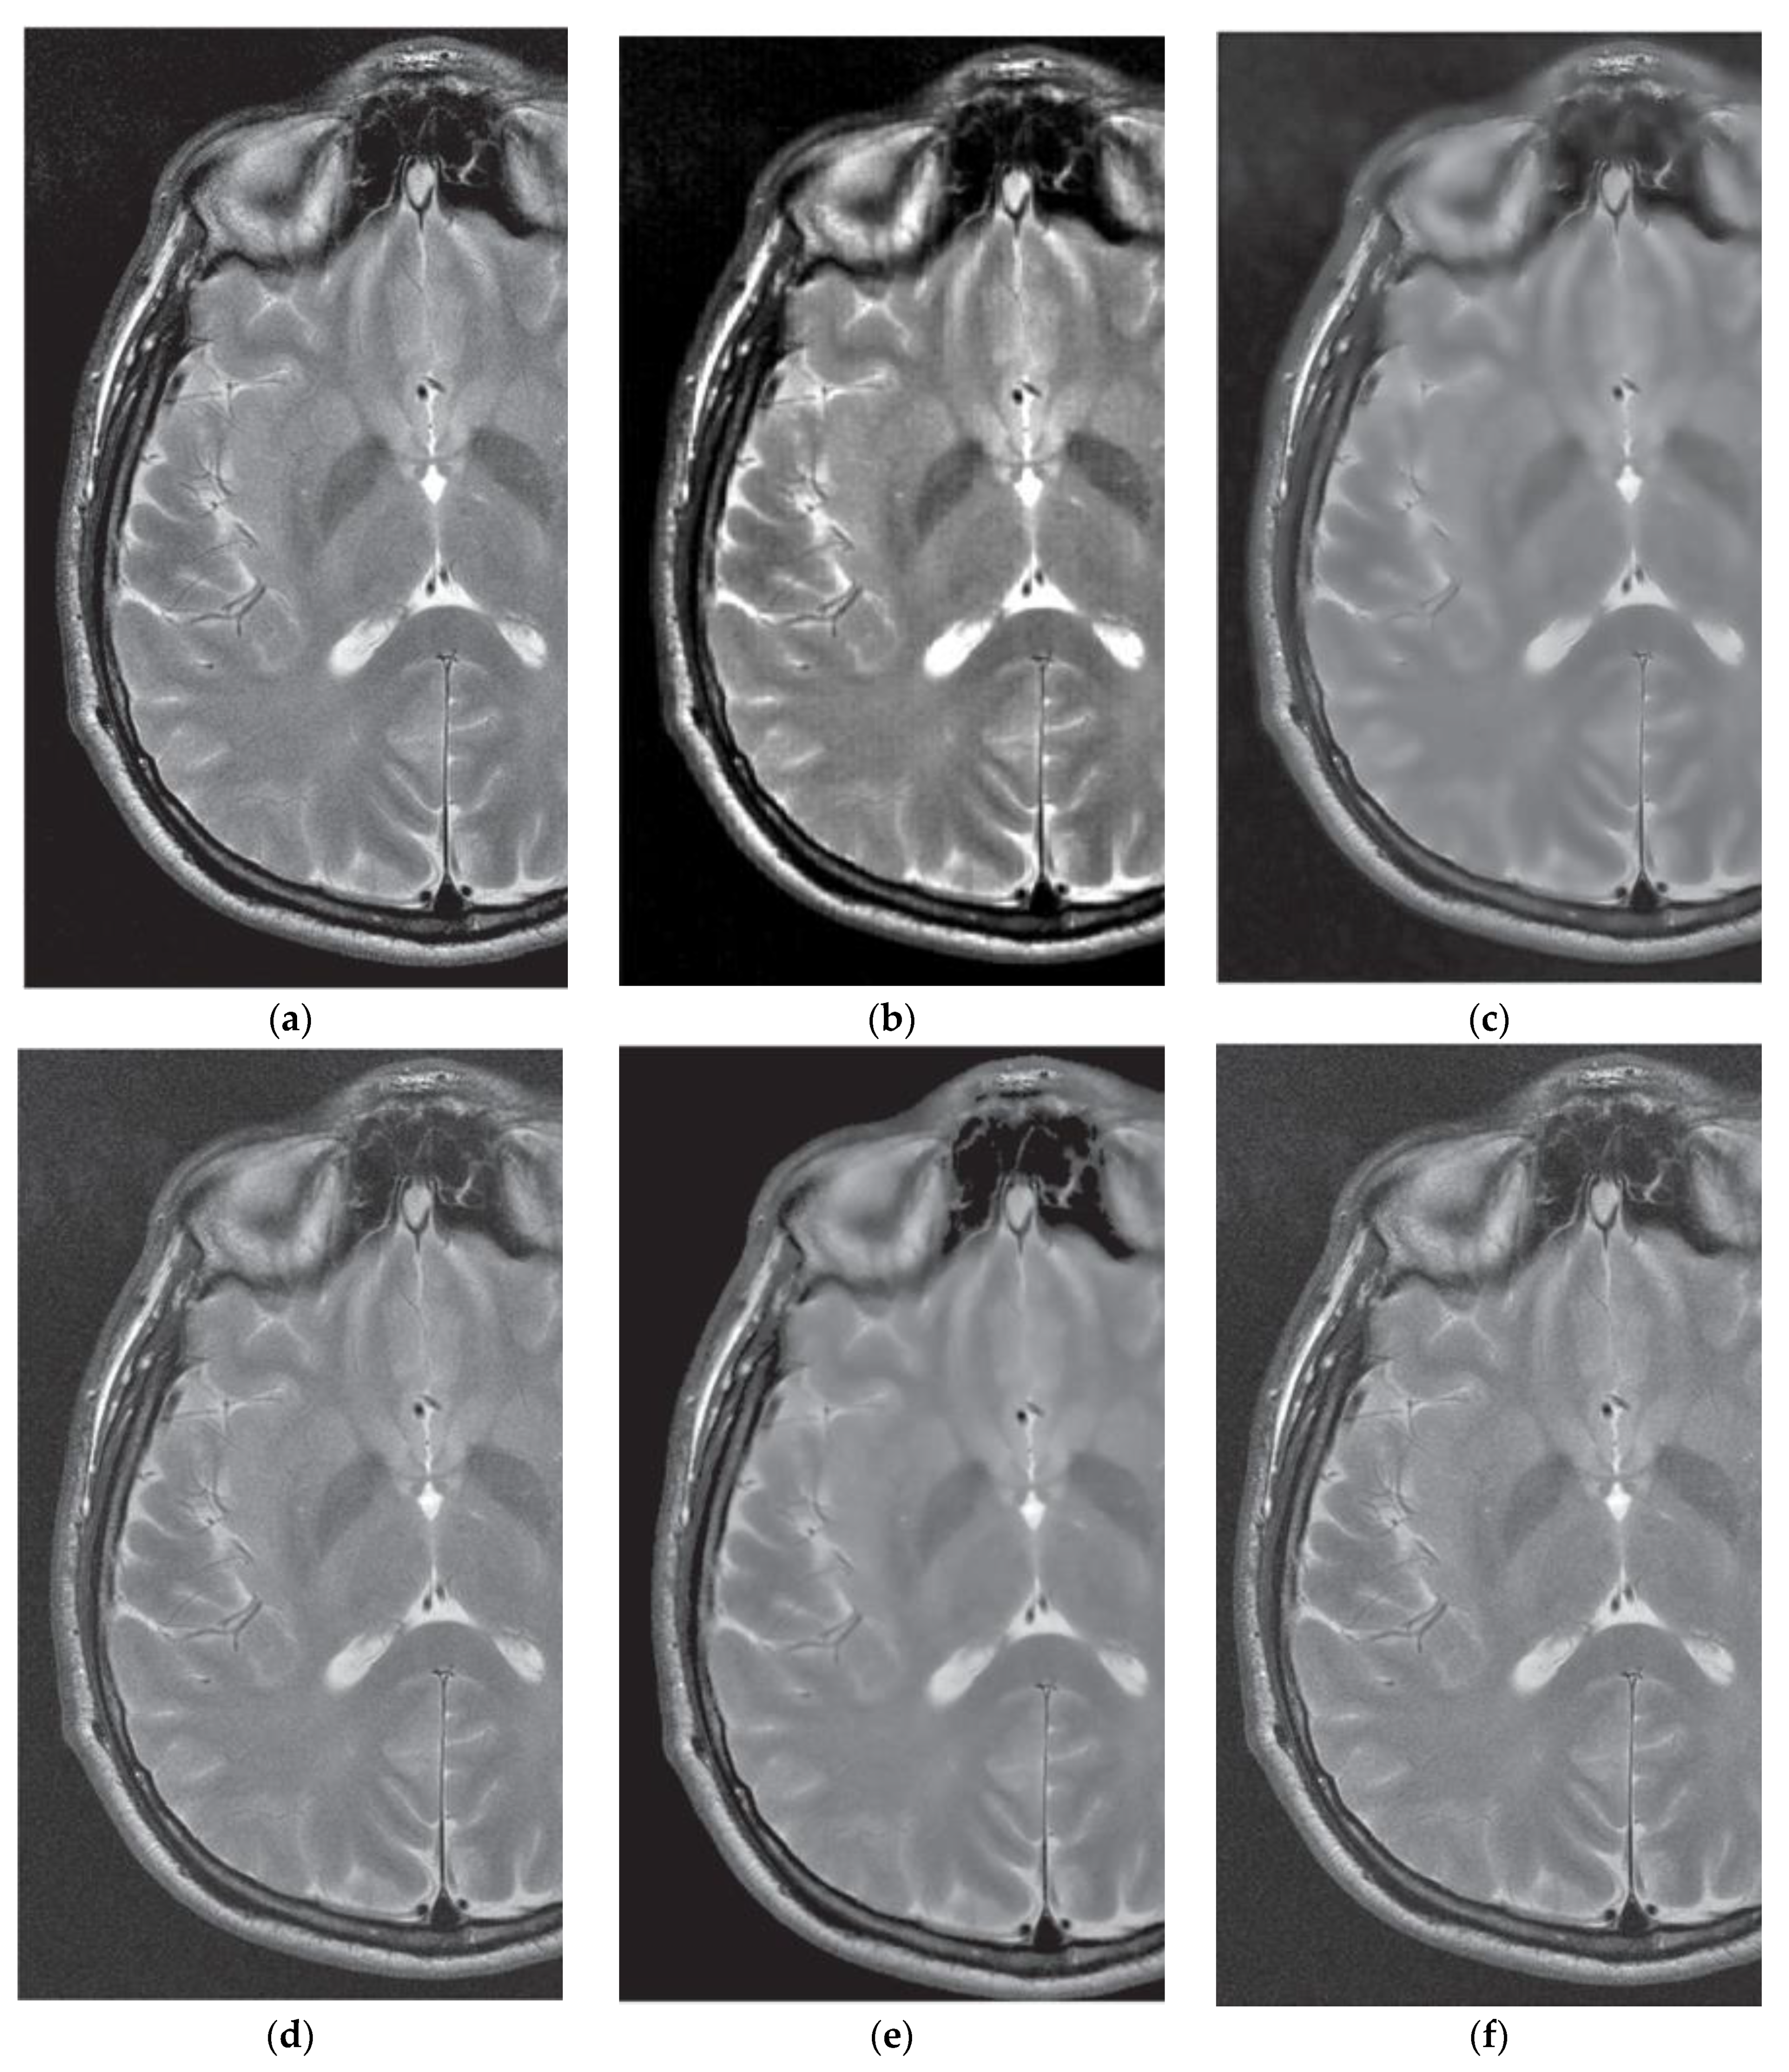

3.3. Comparative Performance in Simulated MRI